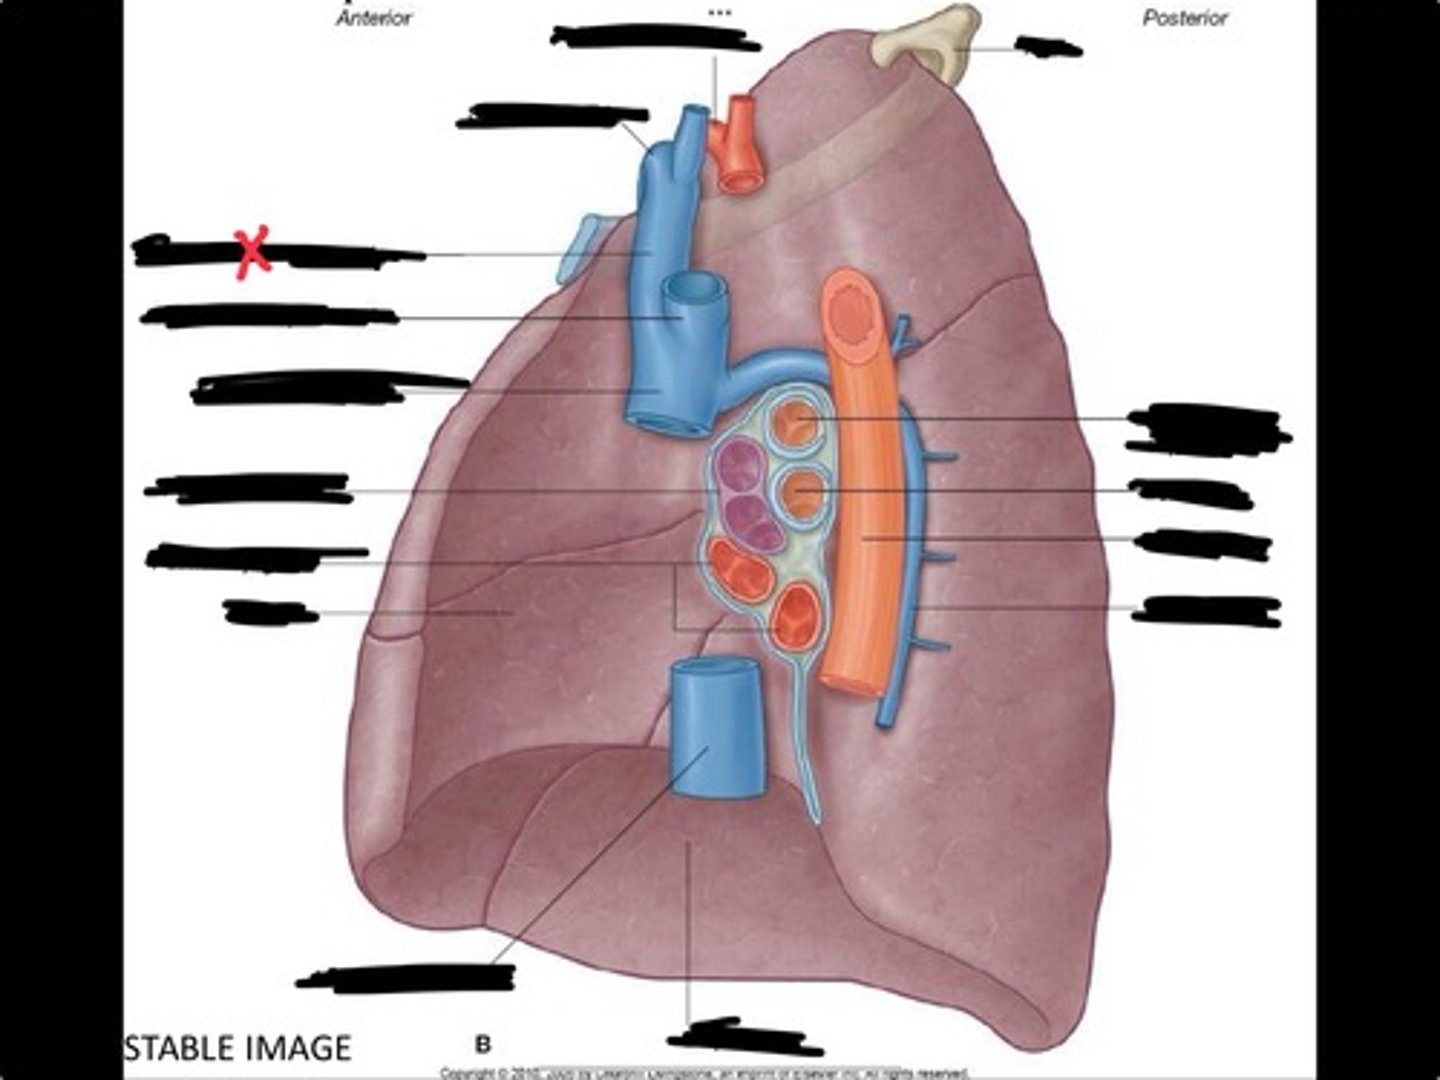

Rib 1

Pulmonary artery

Bronchus to superior lobe

Pulmonary veins